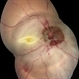

By Vishal Agrawal, MD, FRCS,FACS,FASRS

Agrawal Hospital , Jaipur - Uploaded on Oct 22, 2022.

- CLARUS 700

- 67 yr old male , post PPV for retinal detachment ( 5 years ) presented with sudden DOV . On examination posteriorly dislocated 4 loop haptic iol - bag complex was noted .